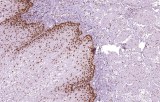

Primary antibodies for immunohistochemistry (IHC) with CE/IVD marking are essential reagents in diagnostic and research pathology, enabling the specific detection of target antigens in formalin-fixed paraffin-embedded (FFPE) tissue sections.

IHC using CE/IVD primary antibodies is a cornerstone in the characterization of gastrointestinal tumors. These antibodies assist pathologists in distinguishing epithelial from mesenchymal origins, determining tumor subtypes, and identifying primary sites in metastatic disease.

- In colorectal cancer, antibodies against cytokeratins (CK7, CK20) and transcription factors such as CDX2 facilitate accurate tumor classification and subtype differentiation.

- In gastric and esophageal adenocarcinomas, IHC highlights metaplastic and dysplastic changes, supporting early detection and prognostic evaluation.